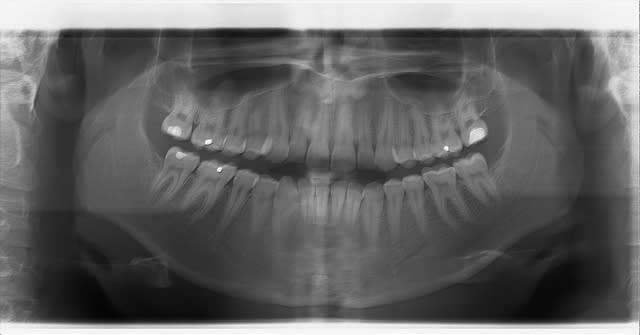

Mon endo de la semaine (je fais rarement plus d'une endo par semaine !)Joli canal lattéral.

Pour la 45, j'y touche pas si un jour besoin, pas mon truc les double courbes.